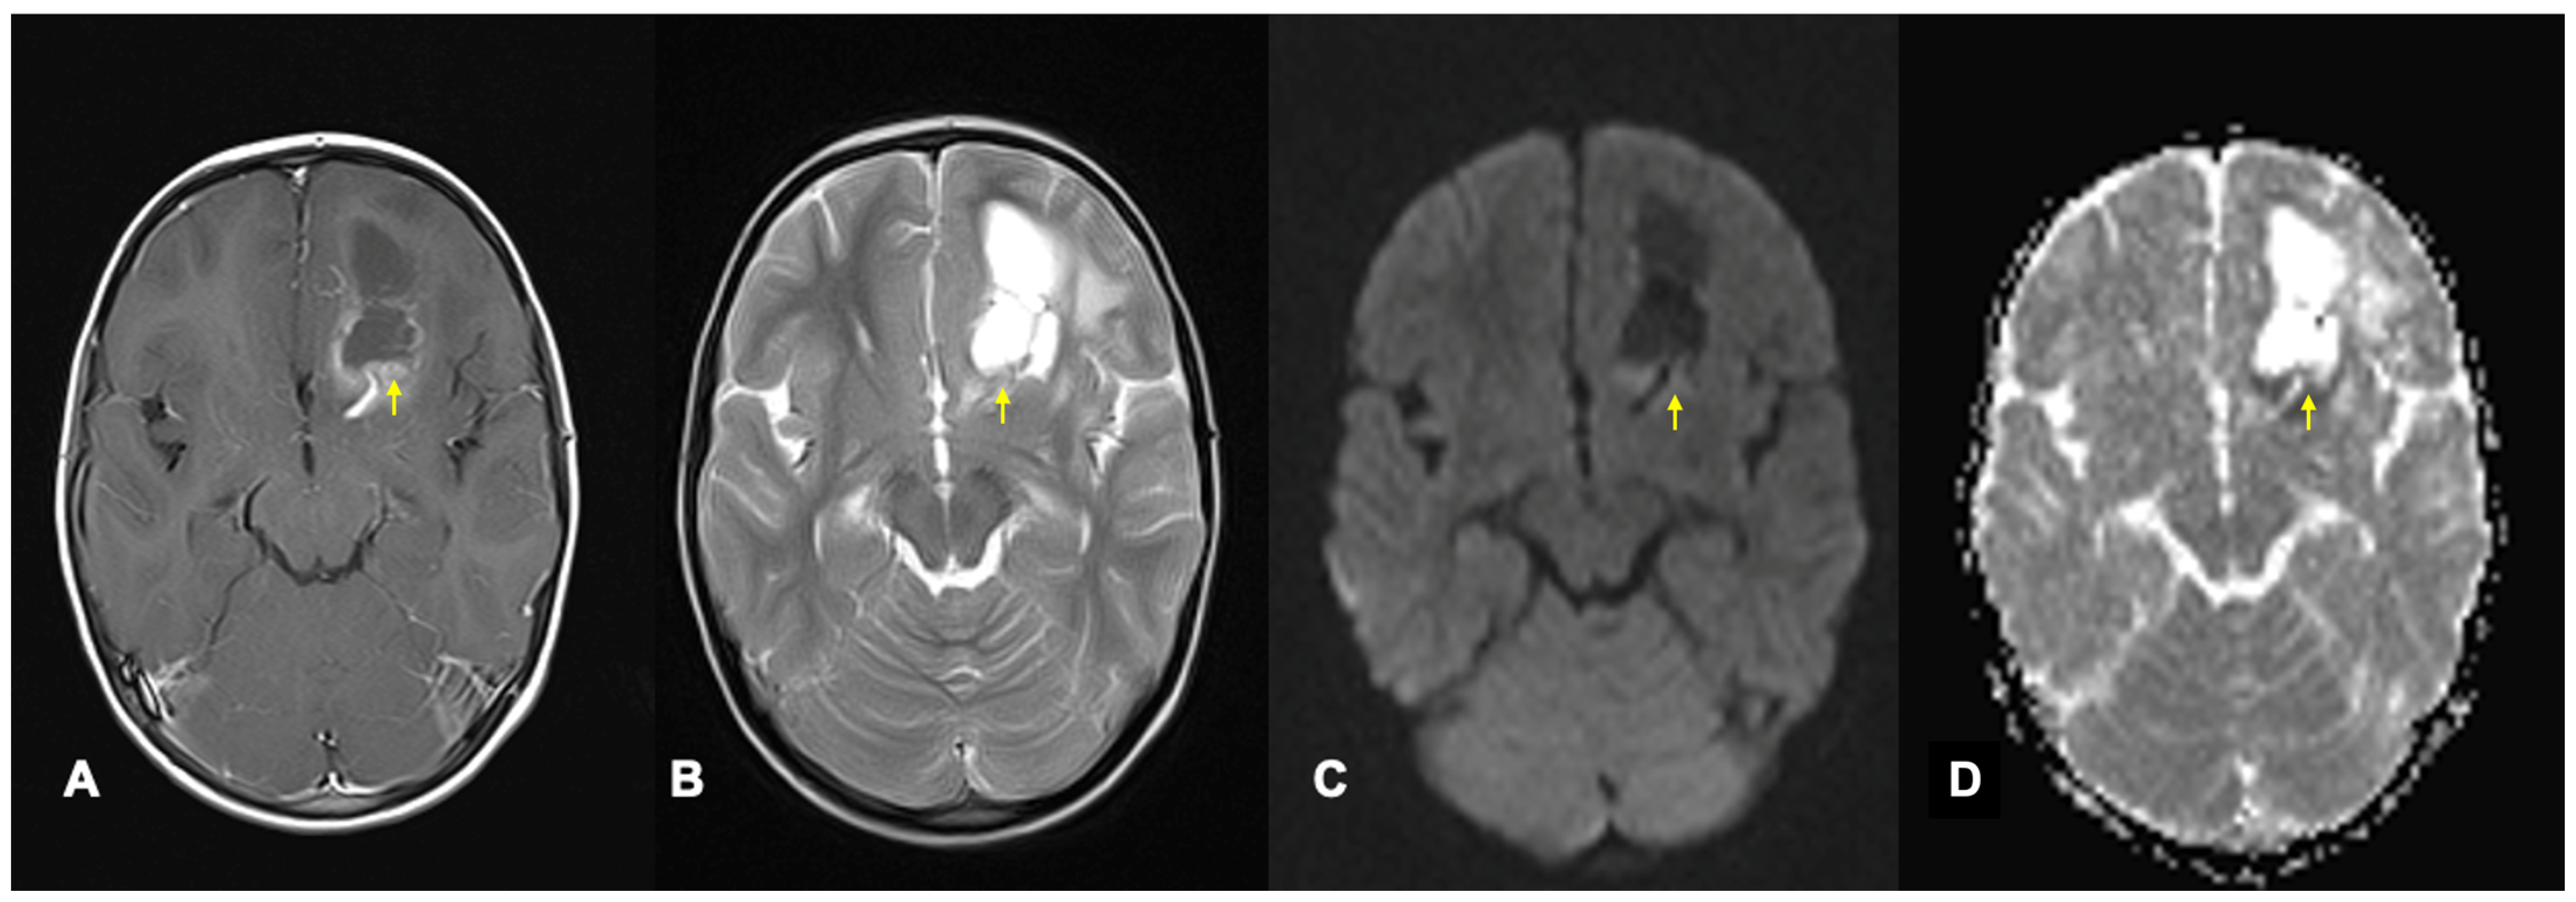

- Shen, J.M.; Xia, X.W.; Kang, W.G.; Yuan, J.J.; Sheng, L. The use of MRI apparent diffusion coefficient (ADC) in monitoring the development of brain infarction. BMC Med. Imaging 2011, 11, 2. [Google Scholar] [CrossRef]